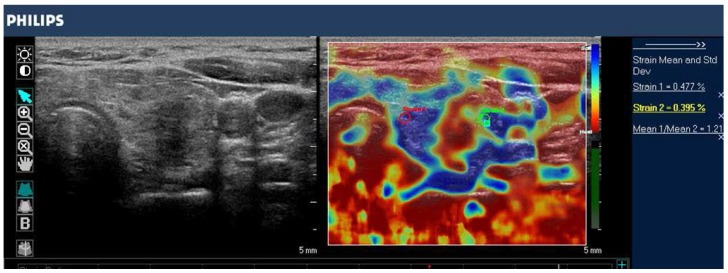

در SWI، یک اندازه گیری کمی از سرعت موج برشی (m/sec) یا مدول یانگ (kPa) در یک ضایعه یا به عنوان یک مقدار واحد در یک ناحیه کوچک ثابت مورد علاقه (ROI) یا برای هر پیکسل در یک میدان به دست می آید. کادر نمای (FOV) به صورت نقشه رنگی 19، 67 نمایش داده میشود. معمولاً از مقیاس رنگی از 0 (آبی تیره = نرم) تا 180 کیلو پاسکال (قرمز = سخت) در سینه USE 73 استفاده میشود (شکل 7).

نمایش کنار هم از تصویر آناتومیک B-mode ایالات متحده (سمت چپ) و نقشه رنگی روکش شده از اندازه گیری امواج برشی همزمان (سمت راست) یک ضایعه پستان که با 2D-SWE در SuperSonic Imagine (SSI) AixplorerTM به دست آمده است. در این سیستم رنگ قرمز نشان دهنده بافت سفت و رنگ آبی نشان دهنده بافت نرم است. ضایعه هیپواکوئیک مشکوک (در داخل مستطیل در تصویر حالت B نشان داده شده است) دارای حاشیه نامنظم، حاشیه های زاویه ای، کمی پهن تر از ارتفاع است و سایه های آکوستیک خلفی را نشان می دهد. الاستوگرام اتیولوژی بدخیم را به دلیل افزایش سفتی (قرمز/زرد/سبز) پیشنهاد کرد و آدنوکارسینوم مجرای در بیوپسی بعدی تایید شد. تصویر توسط دکتر اسمار سایتو.